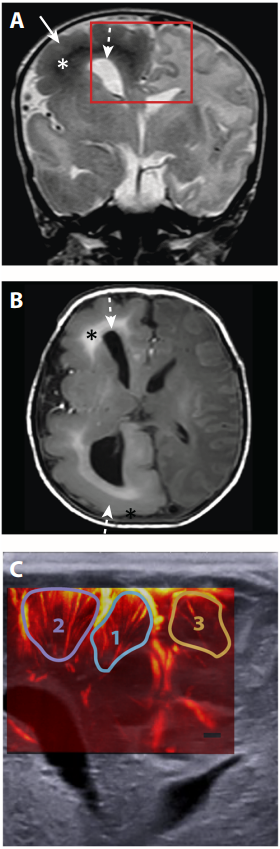

Figure 2: Spatial correlation between UfD signal and ictal events in a newborn with TSC. (A and B) Coronal T2–weighted (A) and axial T1–weighted (B) MRI images where that arrows indicate enlargement of the right hemisphere. Diffuse abnormal white matter signal (*) and enlarged and dysmorphic right lateral ventricle (dashed arrow) are also evident. The red frame depicts the area imaged with fUSI. (C) Representative UfD image (colored) overlaid onto an ultrasound B-mode image (black and white), coloured circles represent three regions in the cortex: #1 and #2 in the right hemisphere and #3 in the left hemisphere (contralateral). From Demene, C. et al., Sci. Transl. Med., eaah6756 (2017). Image and caption adapted with permission from AAAS.

Baud and co-authors then moved to imaging brain activity in neonates with abnormal cortical development in a case of tuberous sclerosis complex (TSC). The technique mapped the spatial increases in blood volume to ictal electrical activity during seizures in the affected hemisphere, compared to the contralateral area. In a patient with cortical dysplasia, the authors found a correlation between the fast spikes in brain activity and slower waves of vascular dynamics where the frequency and amplitude of the signal propagation was higher in the ipsilateral hemisphere, than in the contralateral area. The results point to the ability of fUS data to spatially map the anatomical location of the source of seizures. A main point of interest in fUSI is that the data is three-dimensionally mapped with high fidelity (no motion artefacts were detected in this study) and at millimetre resolution. Instead EEG signals cannot be mapped and compared to an fMR or B-mode US image (Figure 2); rather, the detection of spatial differences relies on the positioning of the electrodes ahead of taking the measurements.